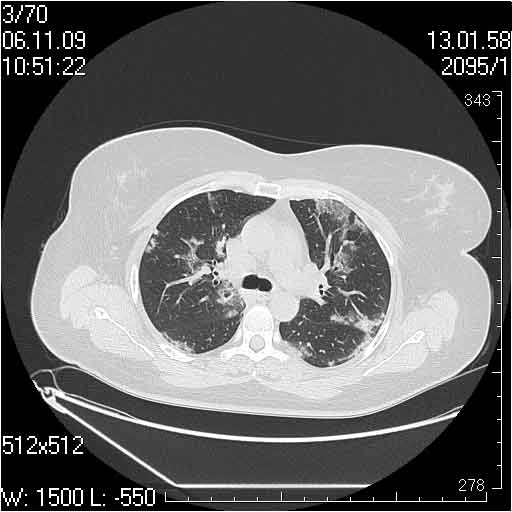

Случай №2

Мужчина 54 лет

Случай 2: картина патологических изменения довольно типична: GGOs & thickened interlobular septas = "crazy paving" sign. Наличие плотностей по типу матового стекла в сочетании с утолщением междолевых перегородок, даёт признак булыжной мостовой; на первом месте будет стоят диагноз альвеолярных протеиноз.